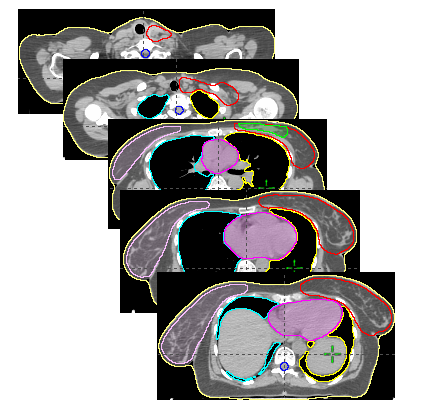

Case diagnosis:Left Breast Cancer

Treatment Site: Left breast with axilla and supraclavicular lymph nodes

Target: PTV_TOT_EVAL

Techniques: 3D-CRT, IMRT, VMAT

General plan criteria were set: # of fields, single isocenter, energies, … etc